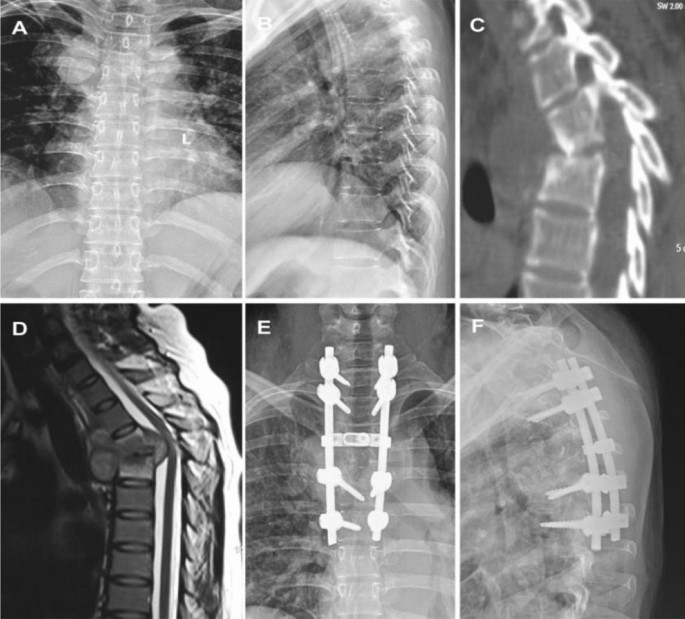

All patients were intubated under general anaesthesia. Patients were placed in a prone position and a posteromedial incision was made to expose the vertebral plate, facet joints and costovertebral joints. After locating the lesion using C-arm fluoroscopy, pedicle screws were inserted in the healthy vertebral body adjacent to the upper and lower affected vertebrae, followed by kyphosis correction. From the costovertebral joints or pedicles of the vertebral arch, the lesion in the anterior vertebral body was removed, as were as the dead bone, necrotic intervertebral disc and caseous necrotic tissue. An autogenous iliac bone graft was then embedded into the focal zone (Fig. 1). After the operation, conventional bacterial cultivation and pathological diagnosis were performed.

The patient (female; 43 years old) presented with thoracic tuberculosis at T3-4 and underwent single posterior debridement, bone graft fusion and instrumentation. (A, B): X-ray in the positive and lateral position before surgery; (C, D): preoperative CT and MRI examination; (E, F): x-ray in the positive and lateral position after surgery.